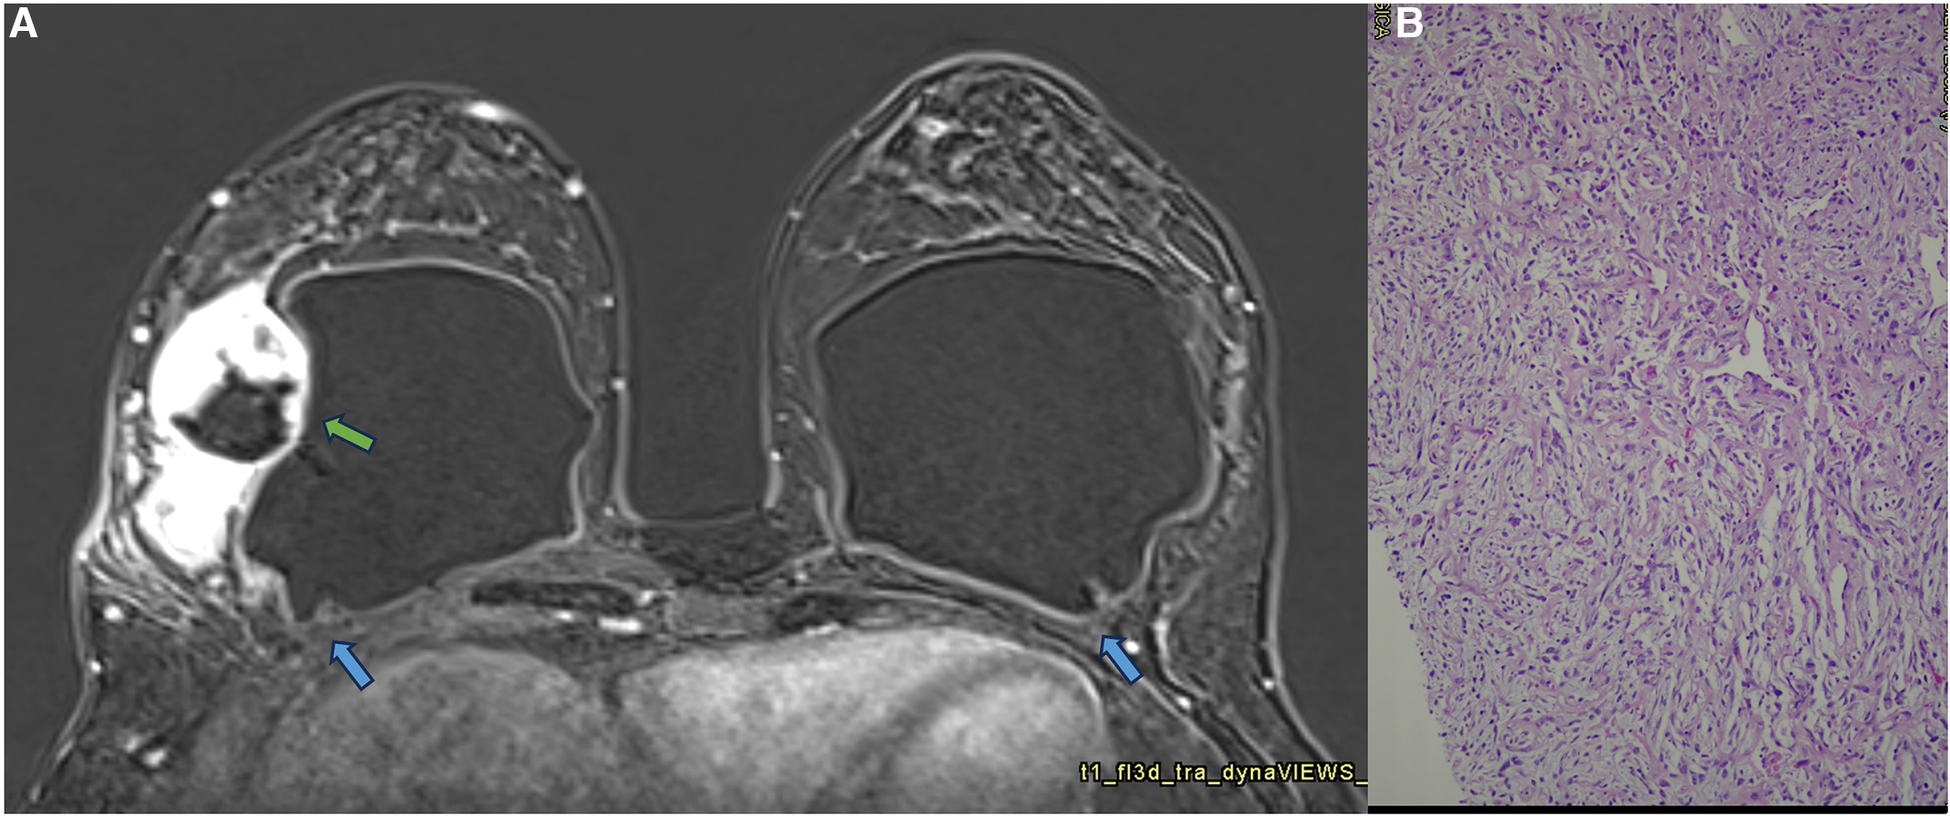

Recently, some cases of breast implant–associated diffuse large B-cell lymphoma (BIA-DLBCL) have been reported in the medical literature. BIA-DLBCL is composed of cellular heterogeneity where the presence of giant B cells stands out. Some studies associate BIA-DLBCL with Epstein–Barr virus (38–40). Magnetic resonance imaging is the method of choice for diagnosing BIA-ALCL and BIA-DLBCL, and it is worth noting that any new lesion compromising the pericapsular environment and presenting contrast enhancement should be considered suspicious. The enhancement of these lesions indicates cellular metabolic activity (Figure 7).

Figure 7. A 47-year-old woman with a palpable lump in the right breast. The sagittal proton density image (A), axial post-contrast MRI image (B), and ultrasonography (C) show a pericapsular mass in contact with the fibrous capsule, with moderate enhancement (blue arrows). There is also capsular contracture and SIGBIC (white arrow). The biopsy specimen (D) shows atypical lymphoid proliferation immunophenotype B.